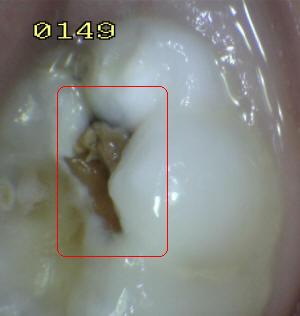

Sistema Internacional para la Detección y Evaluación de Caries (ICDAS)

¿Determine los códigos pertinentes a cada imagen?

Click en el hipervínculo: Para comparar el resultado de su diagnóstico